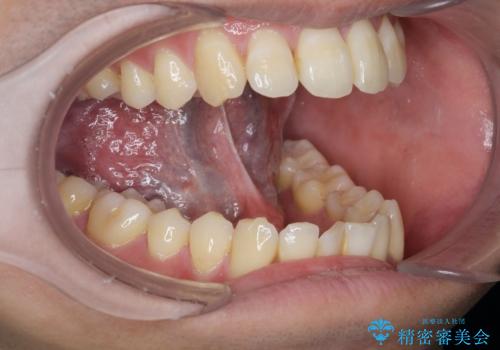

[ 舌小帯の形成 ] 滑舌を改善したい

担当医 大元洋佑

![[ 舌小帯の形成 ] 滑舌を改善したいの症例 治療前](https://seimitsushinbi.jp/wp/wp-content/uploads/2022/10/fa797540f242dace21c05a8161580df4-500x350.jpg?v=1665555891)

![[ 舌小帯の形成 ] 滑舌を改善したいの症例 治療後](https://seimitsushinbi.jp/wp/wp-content/uploads/2022/10/45c8c51b664db205e71949fb1e2ec432-500x350.jpg?v=1665555859)